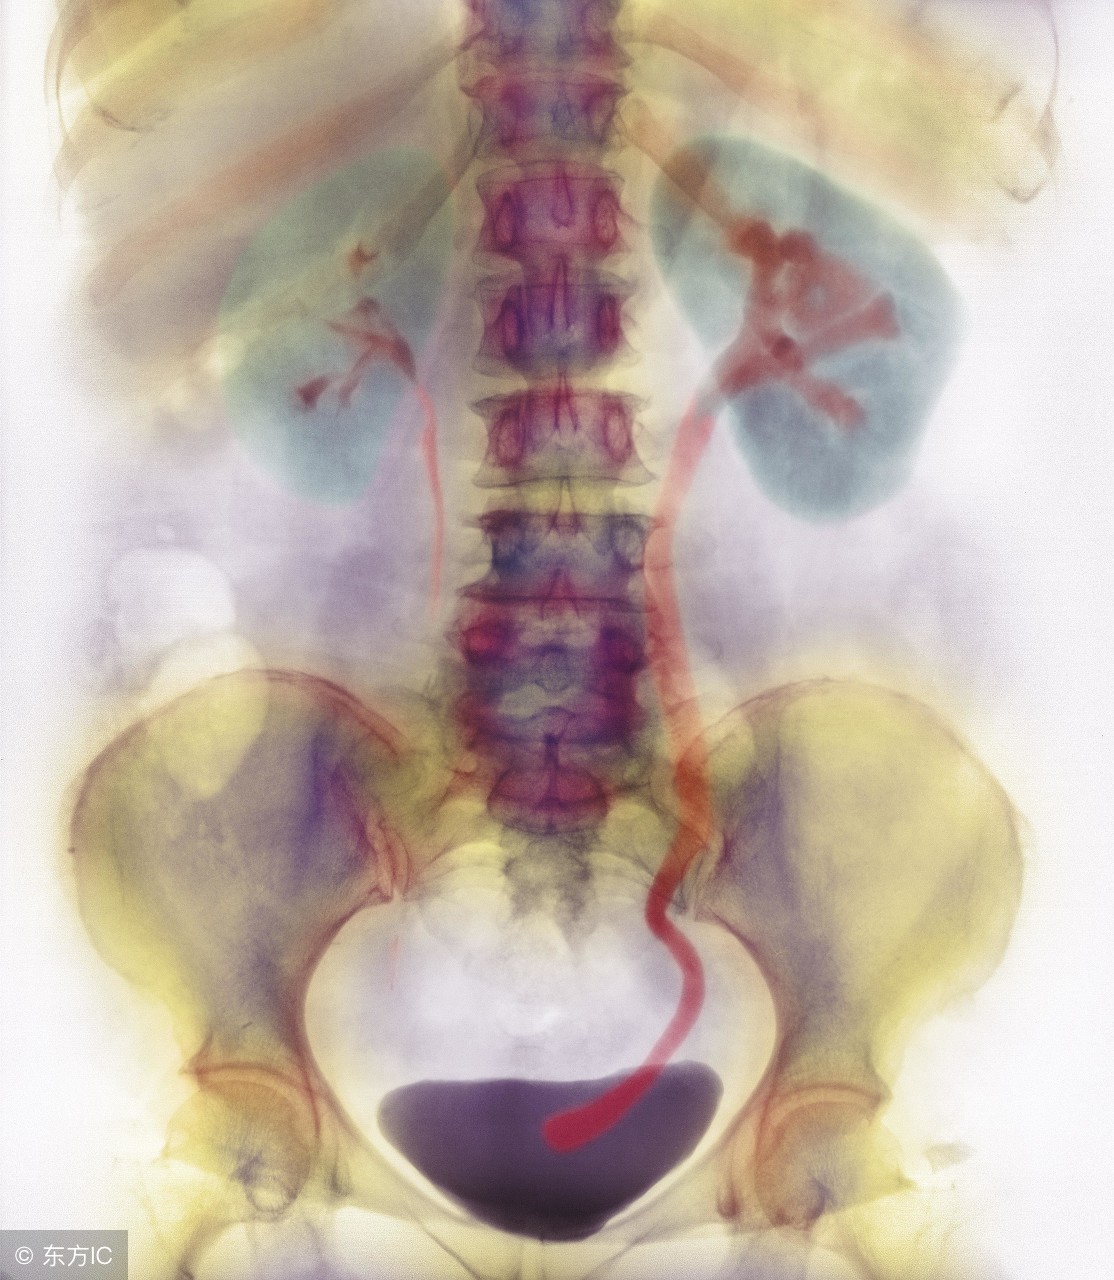

提起输尿管结石,相信大家都并不陌生。输尿管结石是常见的结石疾病,除了肾结石和胆结石之后,输尿管结石最为常见。但是对于输尿管结石,大家是否对其治疗方法并不了解呢?现今治疗方法多样,对于输尿管结石,主要有以下的几种治疗的方法:

一、非手术治疗:适用于结石小于l厘米,结石位置有向下移动倾向、肾功能无明显影响、无尿路感染的患者。大量饮水,服用中药药剂,应用解痉剂、跳跃活动等。

二、输尿管套石:在膀肮镜下用套石篮将结石拉出。适用于小的活动性的中下段输尿管结石。

三、输尿管镜下取石或碎石:输尿管扩张后放人输尿管镜,见到结石用液电或超声碎石器碎碎之,结石也可直接用取石钳取出。

四、体外冲出波碎石:主要适用于上段输尿管结石。

五、手术输尿管切开取石:适用于以上疗法无效,结石大于l厘米,且表面粗糙不能自行排出者,或有输尿管狭窄及感染的患者,能起到好的疗效。